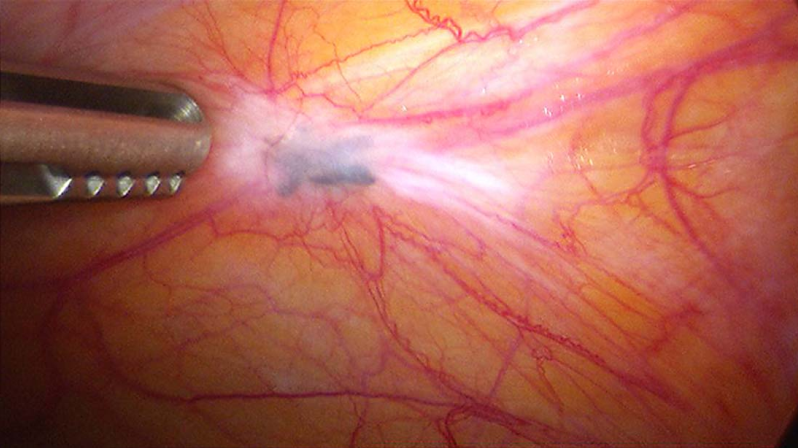

(2)腹膜型内异症( peritoneal endometriosis):分布于盆腔腹膜和各脏器表面,以子宫骶骨韧带、直肠子宫陷凹和子宫后壁下段浆膜最为常见。在病变早期,病灶局部有散在紫褐色出血点或颗粒状散在结节。随病变发展,子宫后壁与直肠前壁粘连,直肠子宫陷凹变浅,甚至完全消失。输卵管内异症多累及管壁浆膜层,累及黏膜者较少。输卵管常与周围组织粘连,可因粘连和扭曲而影响其正常蠕动,严重者可致管腔不通,是内异症导致不孕的原因之一。腹膜型内异症亦分为二型:①色素沉着型即典型的蓝紫色或褐色腹膜异位结节,术中较易辨认;②无色素沉着型:为异位内膜的早期病变,较色素沉着型更常见,也更具生长活性。表现形式多种多样,依其外观又可分为红色病变和白色病变。无色素沉着病灶发展成典型的病灶需6~24个月。